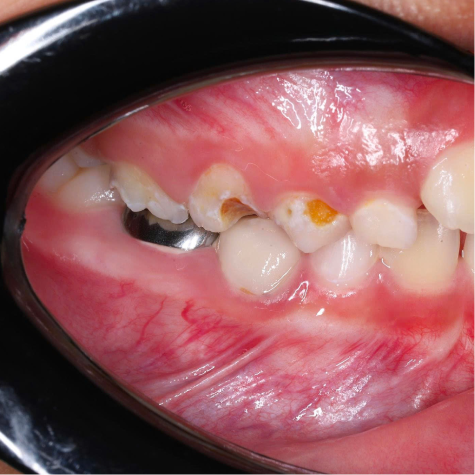

SSC (Stainless Steel Crown) là mão răng bằng thép không gỉ, được thiết kế sẵn với nhiều kích cỡ khác nhau, thường dùng để phục hồi răng sữa đã bị sâu lớn hoặc tổn thương nặng. Đây là một dạng phục hình toàn phần bao phủ toàn bộ thân răng, giúp bảo tồn và duy trì chức năng của răng sữa cho đến khi thay răng vĩnh viễn.

- Bảo tồn răng tối đa

Duy trì được răng sữa đến đúng thời điểm thay răng, ngăn ngừa mất khoảng và sai lệch cung răng.